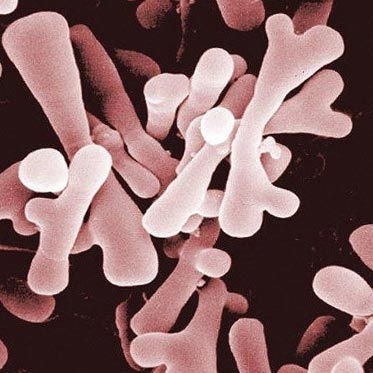

Fig. 13. Bifidobacteria. imagine tridimensională.

bifidobacterii

- acetat de produse bifidobacterii datorate și acid lactic. mediu acidifiat, inhibă creșterea bacteriilor patogene ce provoacă putrefacție și fermentație;

- Datorită bifidobacterii reduce riscul de a dezvolta alergii la produsele alimentare la copii;

- acestea oferă antioxidant și efect anti tumoral;

- Bifidobacteria sunt implicate în sinteza de vitamina C;

- bifidobacterii si lactobacili sunt implicate în procesele de absorbție a vitaminei D, calciu si fier.